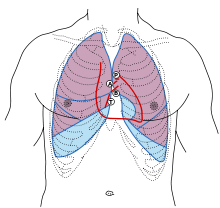

The closing of the mitral valve and the tricuspid valve constitutes the first heart sound (S1). It is not the valve closure itself which produces the sound but the sudden cessation of blood flow, when the mitral and tricuspid valves close.

Apical view of valves

Apical view of valves Cross-sectional view of mitral valve between left atrium (upper chamber) and left ventricle (lower chamber), which shows parts of walls of left atrium and left ventricle that are next to the mitral valve.